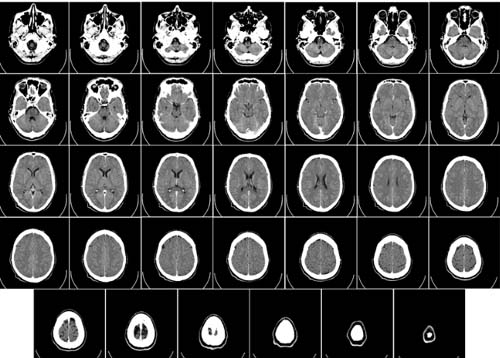

Pesquisa feita em modelos animais para epilepsia (ratos geneticamente selecionados para apresentarem os sintomas) mostrou que a administração crônica do canabidiol (CBD), conseguiu evitar a progressão da doença. Os resultados do estudo – feito na Faculdade de Medicina de Ribeirão Preto (FMRP) da USP – apontam que o tratamento com essa  substância derivada da Cannabis sp. impediu o recrutamento de novas áreas cerebrais no processo que dá origem à epilepsia em novas partes do cérebro. Por isso, evitou-se o aparecimento de crises límbicas (mais graves e associadas a estruturas do cérebro como hipocampo, amígdala e córtex) no modelo que imita o tipo de epilepsia mais frequente em humanos, que é a do lobo temporal.

Inicialmente, o efeito bloqueador foi observado a partir de análises no comportamento dos animais, sendo confirmada uma atenuação das crises. Outra verificação desse efeito foi por meio de uma técnica laboratorial que detectou, em tecidos cerebrais do animal, uma proteína específica, a FosB. Essa proteína se acumula e pode ser quantificada em neurônios ativados cronicamente como na situação característica das crises epilépticas.